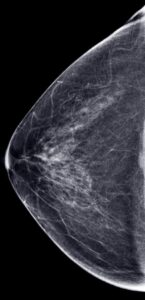

Below are my actual mammogram images from a month before I had my breast augmentation in 2019. My breast tissue is dense (very white) with little fat, so the image does not have much black space.

A mammogram is an X-ray examination of your breast taken from different angles. Mammograms are recommended to start at age 40 and occur yearly to look for signs of cancer or abnormalities in the breast, such as a tumor (mass or lump), calcifications, areas of abnormal density or cysts. On the image, breast tissue looks white on the imaging; fat looks black. Regular mammograms can find signs of breast cancer early such as calcifications, sometimes up to three years before a lump can be felt clinically.